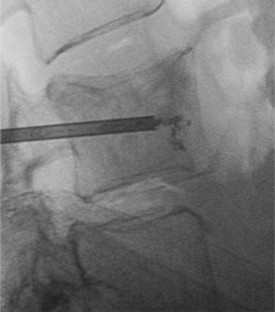

Fig. 1